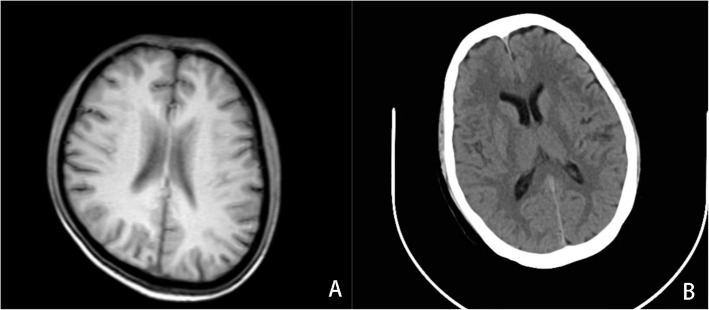

Background: Recently, increased reports reveal that anti-interferon-gamma (IFN-γ) autoantibodies (AIGAs) are strongly associated with several severe disseminated infections. However, reports on AIGAs with central nervous system (CNS) infections are rare. Here, we described three AIGAs-positive adults who had persistent or recurrent disseminated infections caused by Talaromyces marneffei (TM), nontuberculous mycobacteria (NTM), mycobacterium tuberculosis (TB), or other pathogens, accompanied with CNS infections. In addition, we conducted a thorough literature review of AIGAs-positive patients with CNS infections.

Case presentation: We report three HIV-negative cases of recurrent disseminated infections including CNS, and AIGAs were measured. All patients had no history of underlying diseases or immunosuppression and presented with fever, cough, and headache. They were negative for HIV antibodies but positive for AIGAs. The patients were diagnosed with CNS infections based on cerebrospinal fluid (CSF) examination and next-generation sequencing (NGS). All patients received anti-infective treatment according to different pathogens, and their condition remained stable without recurrence.

Conclusions: In adults with severe and recurrent infections of multiple organs without known immunodeficiency, adult-onset immunodeficiency (AOID) associated with AIGAs should be considered. In AIGAs-positive patients, the blood-brain barrier (BBB) may be disrupted, leading to susceptibility to CNS infections.